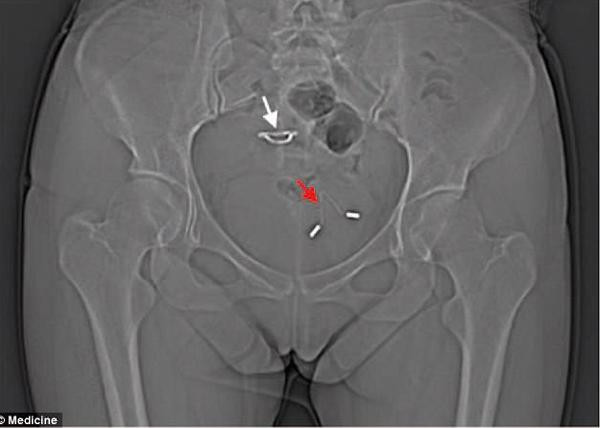

5 năm sau, người phụ nữ này đến bệnh viện kiểm tra vì bị đau bụng và thắt lưng, thường xuyên buồn đi tiểu, trong nước tiểu thỉnh thoảng còn có máu.

Chiếc vòng tránh thai đâm qua tử cung, chui vào bàng quang người mẹ.

Lúc này, các bác sĩ thực hiện chụp X-quang và bàng hoàng phát hiện chiếc vòng tránh thai năm nào đã đục thủng tử cung người phụ nữ, đi vào bàng quang rồi gây ra các biến chứng về đường tiết niệu. Những triệu chứng người phụ nữ này gặp phải chắc chắn do lệch vòng tránh thai gây ra nhưng lý do cụ thể vẫn chưa rõ ràng.